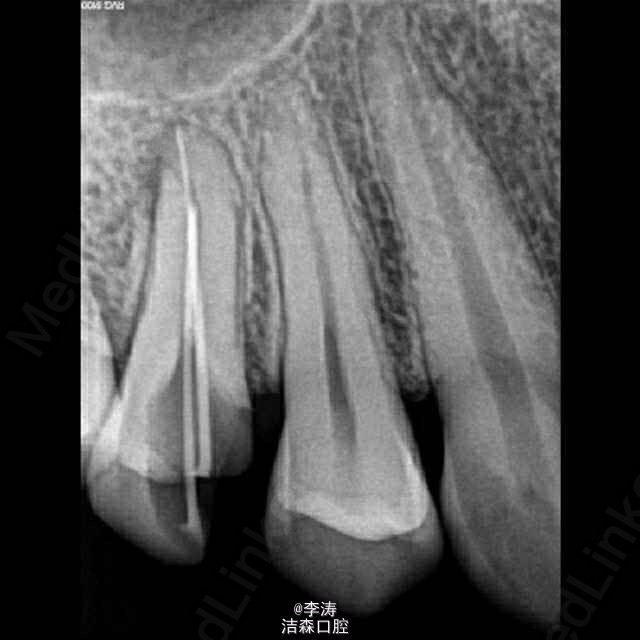

过台阶根管再治疗一例

15牙因根管治疗后牙折裂,行根管再治疗

根管预备形成台阶1例

年轻恒牙;根管再治疗;消除台阶